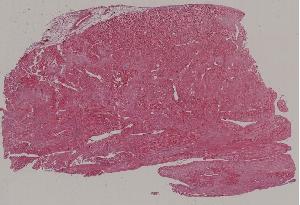

47.心肌梗死

低倍视野